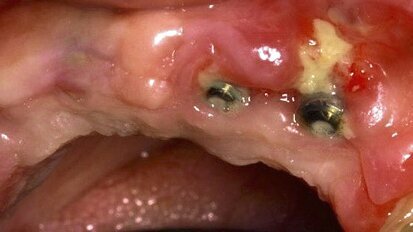

Tecnologías de última generación para el manejo periodontal y perimplantar en paciente adulto mayor

El Profesor José Carlos Rosas, autor del libro “Cirugía piezoeléctrica. Generalidades y aplicaciones clínicas”, muestra en este caso clínico cómo ...